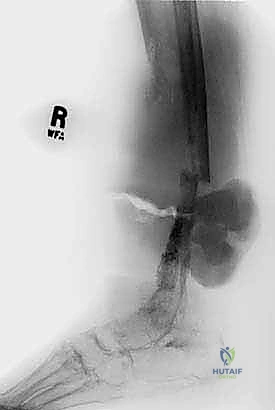

- الأشعة السينية (X-ray): الخطوة الأولى لتقييم العظام وتحديد نمط التدمير العظمي.

- الرنين المغناطيسي (MRI): هو المعيار الذهبي (Gold Standard) لتقييم الأورام. يوضح بدقة امتداد الورم في النخاع العظمي والأنسجة الرخوة، وعلاقته بالأعصاب والأوعية الدموية.

- الأشعة المقطعية (CT Scan): ضرورية لتقييم القشرة العظمية والتكلسات داخل الورم، وللبحث عن أي انتشار في الرئتين.

يعتمد الأستاذ الدكتور محمد هطيف على دراسة هذه الصور الإشعاعية شخصياً قبل تحديد مسار إبرة الخزعة، لضمان عدم تلويث الحجرات العضلية السليمة (Compartments).

لضمان أخذ العينة من الجزء الأكثر تمثيلاً للورم وتجنب المناطق الميتة (Necrotic areas)، يستخدم الدكتور هطيف جهاز الأشعة المقطعية أو جهاز القوس المفلور (C-arm) لتوجيه الإبرة في الوقت الفعلي.

3. إدخال الإبرة واستخراج العينة

يقوم الدكتور بإجراء شق دقيق جداً (لا يتجاوز بضعة ملليمترات) في الجلد. يتم إدخال الإبرة المجوفة عبر مسار تم التخطيط له مسبقاً بعناية فائقة. يتم سحب عدة عينات أسطوانية من أماكن مختلفة داخل الورم لضمان دقة التشخيص.